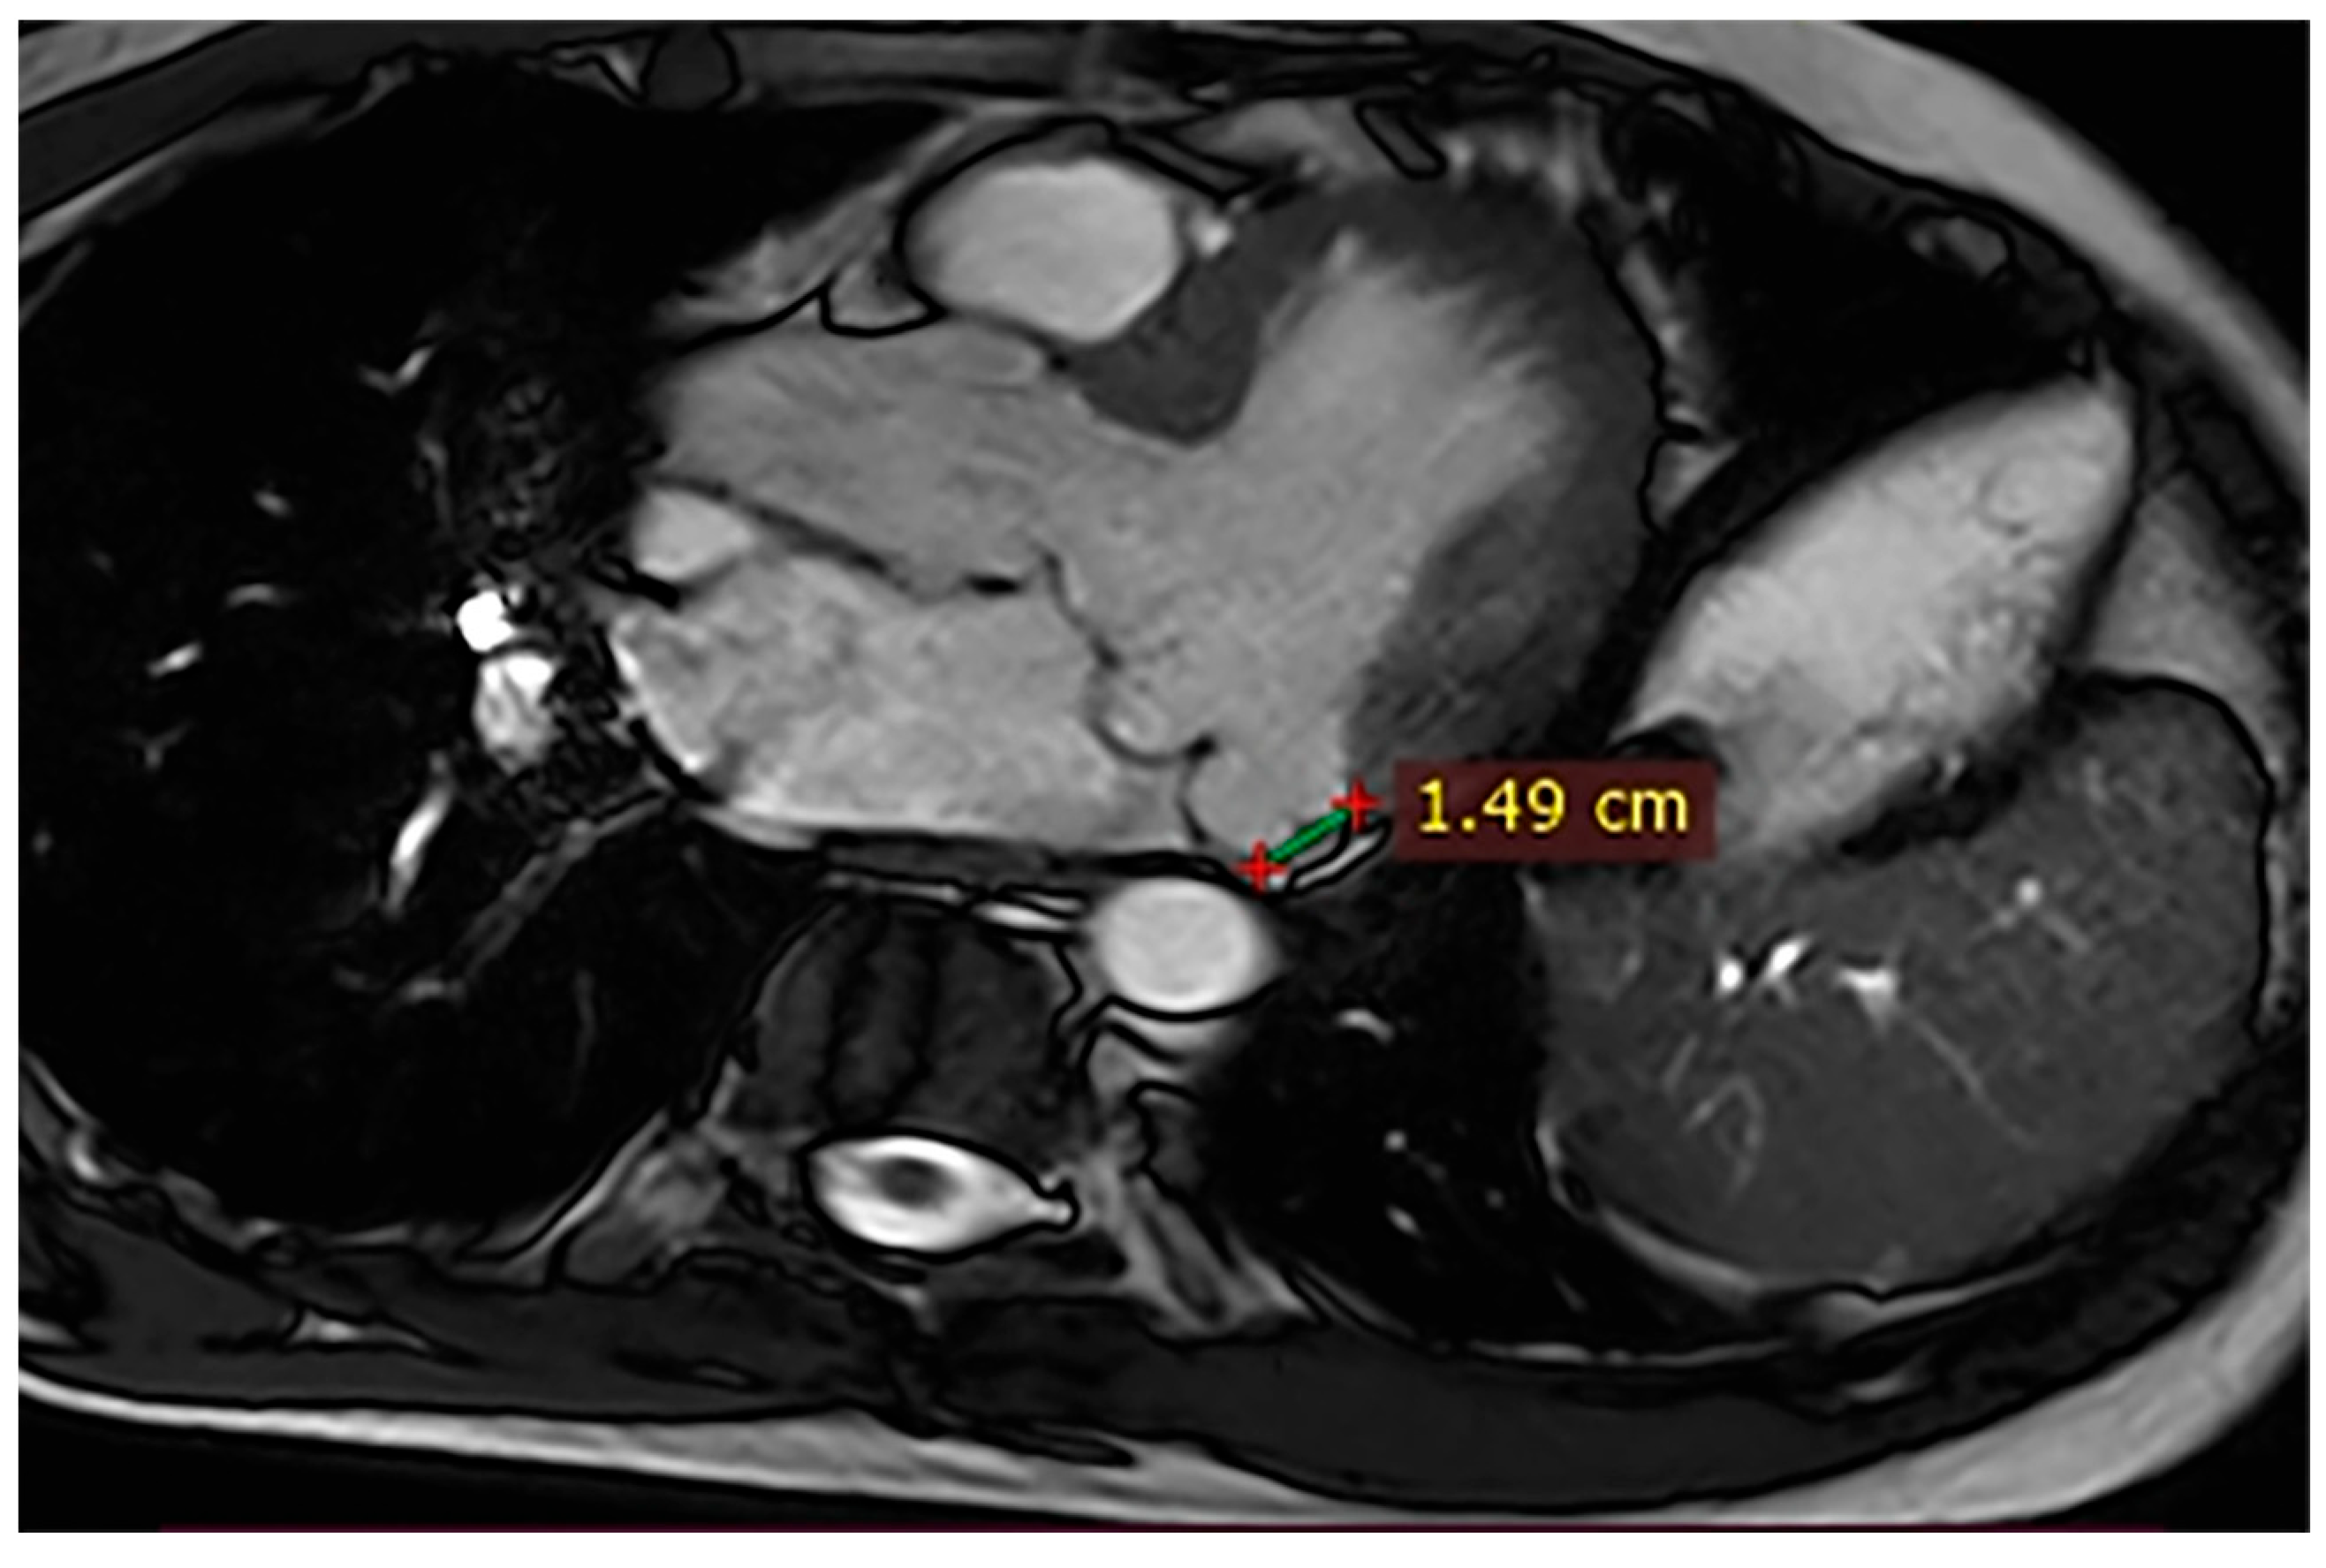

| Case | Patient (Sex, Age) | Symptoms | MAD (mm) | Valvular Issues | LGE | Other Details |

|---|---|---|---|---|---|---|

| 1 | Female, 61 years old | Syncope | 11 | MVP, mitral regurgitation | Lateral | Holter: atrial tachycardia and ventricular ectopy; cardiology follow-up planned for possible mitral valve repair |

| 2 | Male, 52 years old | Syncope and atypical chest pain | 10 | - | Lateral | History of ventricular arrhythmias; cardiology follow-up and Holter monitoring recommended |

| 3 | Female, 74 years old | Extrasystole | 3 | - | No LGE | No LGE; patient reassured and scheduled for periodic clinical follow-up |

| 4 | Male, 34 years old | Extrasystole in Marfan syndrome | 15 | MVP, valvular regurgitation | No LGE | Marfan syndrome; MVP with regurgitation; regular cardiology follow-up advised. |

| 5 | Male, 63 years old | Heart failure | 2,5 | MVP, valvular regurgitation | No LGE | Reduced LVEF (47%) with left atrial dilatation; heart failure therapy optimized; follow-up planned. |

| 6 | Male, 68 years old | Palpitations | 5 | - | Lateral | LGE in basal lateral wall; electrophysiological evaluation and ECG monitoring recommended. |

| 7 | Female, 53 years old | Extrasystole and syncope | 15 | MVP, valvular regurgitation | Basal-lateral | Extensive MAD with MVP and LGE; increased arrhythmic risk; antiarrhythmic therapy considered. |

| 8 | Female, 63 years old | Aortic and mitral regurgitation | 11 | Aortic and mitral regurgitation | Lateral | Aorto-mitral regurgitation with septal hypokinesia; mitral valve repair performed; heart failure therapy started. |

| 9 | Male, 45 years old | Palpitations and vertigo | 10 | - | Lateral | Basal lateral LGE; regular clinical and ECG follow-up recommended |